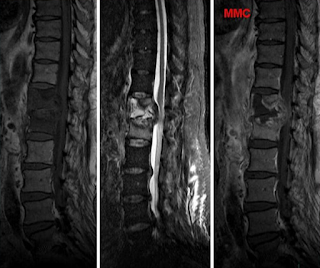

cas n°5

5- Spondylodiscite